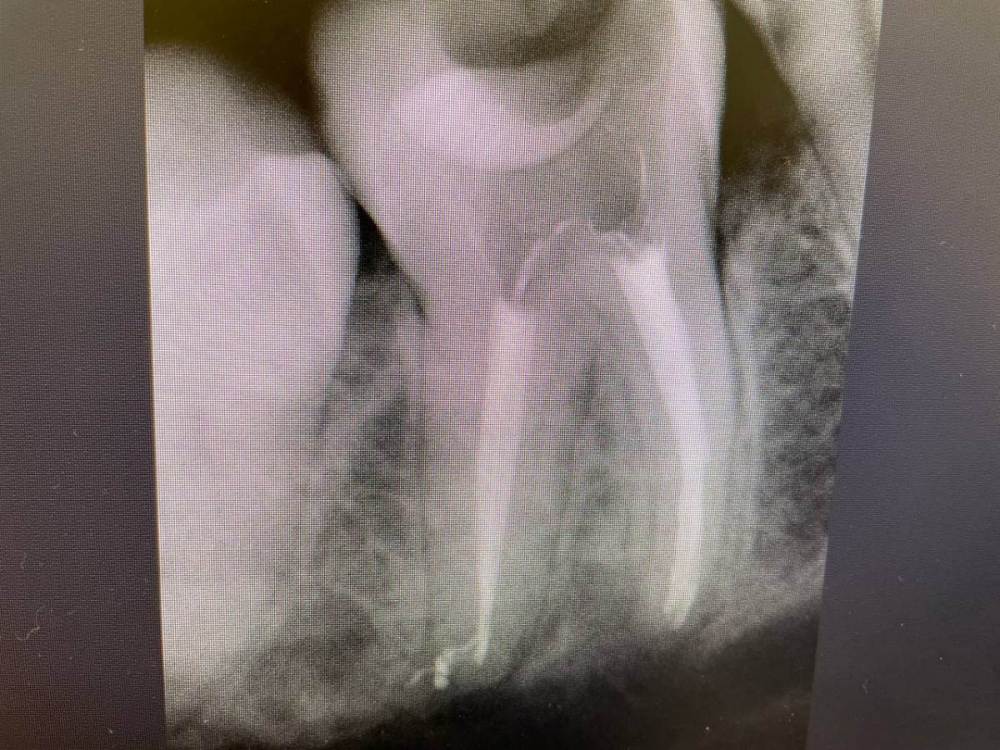

1586Doc Опубликовано 8 декабря, 2021 Автор Поделиться Опубликовано 8 декабря, 2021 Добавим эндо) Ретрит 46 зуб, 2 фрактуры в медиальных каналах. Один достаем, второй обходим )) 1 3 Ссылка на комментарий